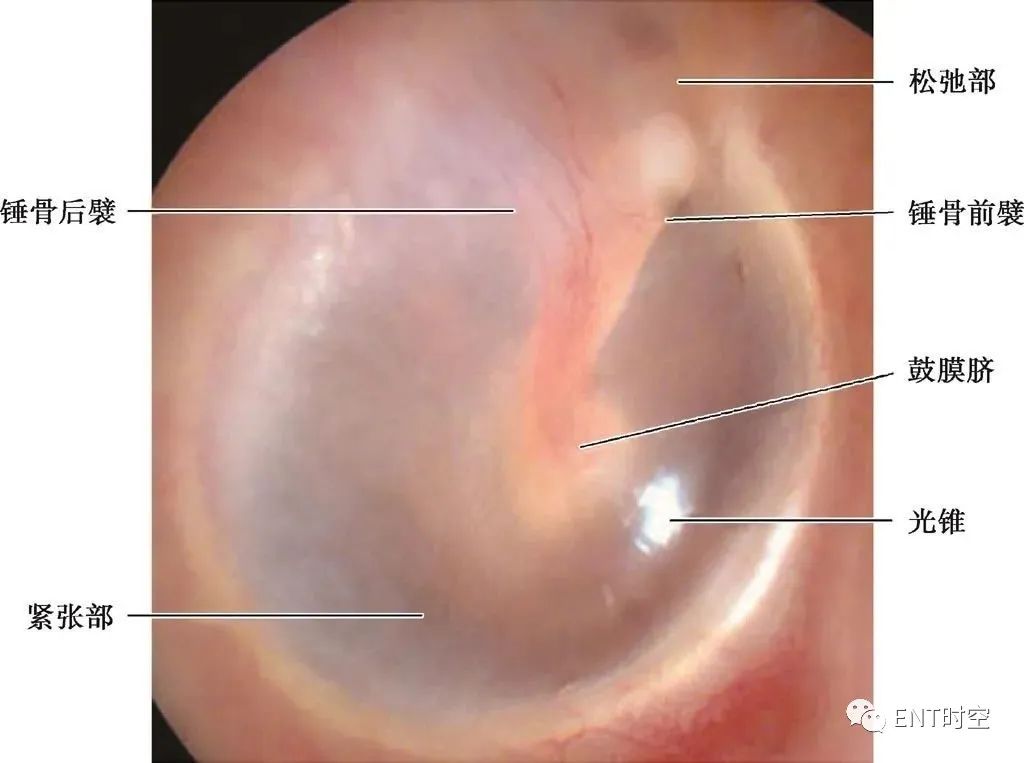

鼓膜正常结构

鼓膜(右侧)